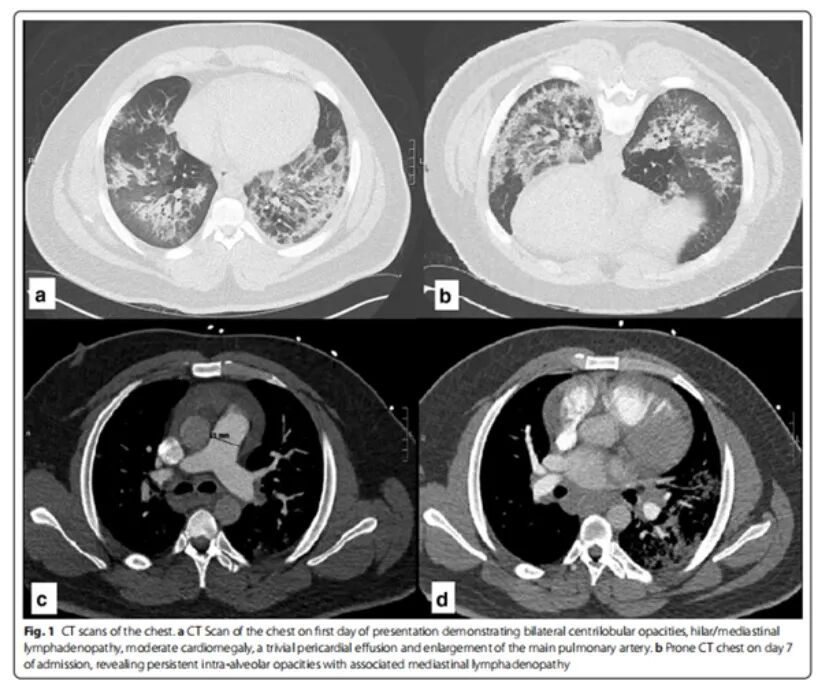

6个月后出现高血压急症、心衰,心脏彩超示射血分数25%,心包积液。复查ANCA及相关免疫指标仍阴性。肾脏活检:肾小球硬化、毛细血管闭塞、管壁增厚。予激素及利妥昔单抗治疗。病情进展为透析依赖的终末期肾病,同时伴有胰腺炎、假性动脉瘤、腹膜后血肿、心包填塞。[Mollaeian A, et al. Auto Immun Highlights, 2021, 12(1):1.]

图片